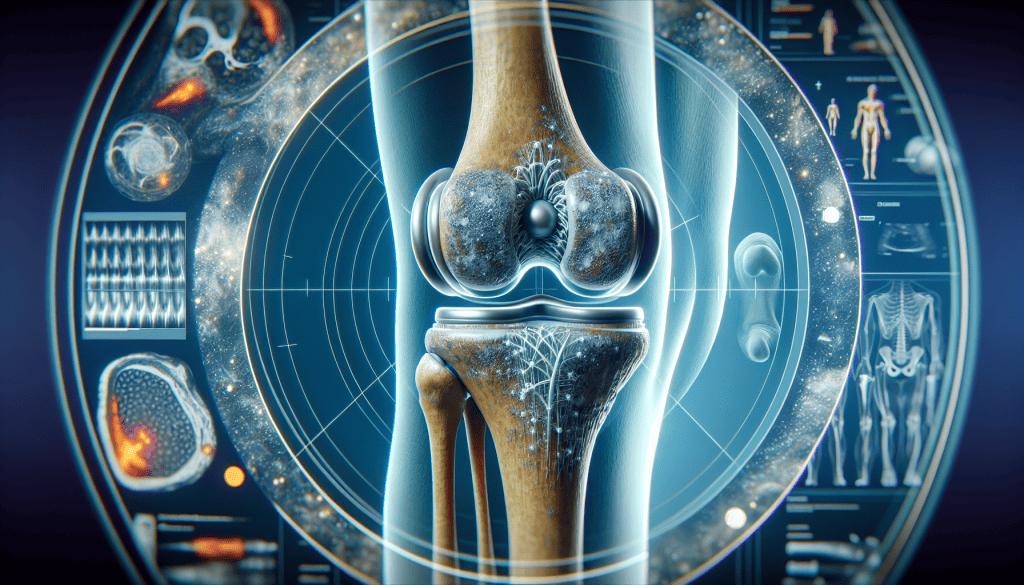

Ortezan - trajno ublažavanje bola u koljenu

- otkloniti kronični bol u koljenima

- poboljšati regeneracijske procese mišića, tetiva i ligamenata i do 86%,

- poboljšati rad lokomotornog sustava i povratiti 100 % pokretnosti

- riješiti se ukočenosti i krutosti zglobova

- spriječiti degeneraciju poboljšanjem stabilnosti zglobova i ligamenata

- imati tri puta više energije

- omogućava smanjivanje oteklina, bola i ukočenosti koljena

- 100% je bezopasna za tijelo i ne opterećuje organizam otrovnim kemikalijama